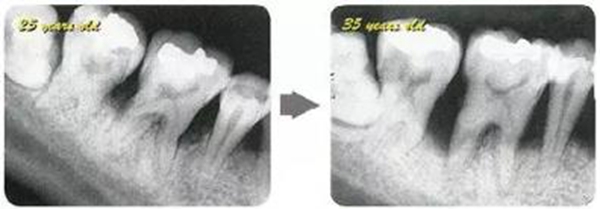

牙周病的發(fā)展因部位不同而發(fā)展程度不同的。10點(diǎn)后的狀態(tài)參考病例①和參考病例②的磨牙處的狀態(tài)相比較,思考下沒(méi)接受治療病情發(fā)展的特別性吧。

參考病例① 35歲女性

在左下第一磨牙在25歲時(shí)近中處可以看到垂直性的骨吸收,但35歲時(shí)吸收停止,原本沒(méi)有見(jiàn)到的遠(yuǎn)中處骨吸收的,現(xiàn)在卻吸收得很嚴(yán)重。

在右下處,原本有大量骨吸收的第一磨牙處的吸收卻變緩慢,原本沒(méi)有吸收的第二前磨牙卻出現(xiàn)了吸收。出現(xiàn)吸收的左上第一磨牙的遠(yuǎn)中處,吸收得越來(lái)越多了。

把10年間的變化做成表格。牙周病的發(fā)展根據(jù)各個(gè)人會(huì)不同,即使通一個(gè)人,不同牙齒,不同牙面發(fā)展的狀態(tài)也不同。